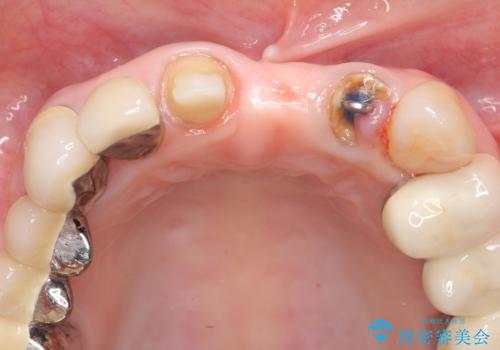

- 前歯の審美障害、見た目の改善を希望され来院されました。

歯肉縁下カリエスも認められるため、挺出を行いセラミックブリッジを審美的に新製します。

- 47万円(仮歯×3・ファイバーコア×2・ジルコニアクラウン×3 歯の挺出)費用は治療当時の料金となります